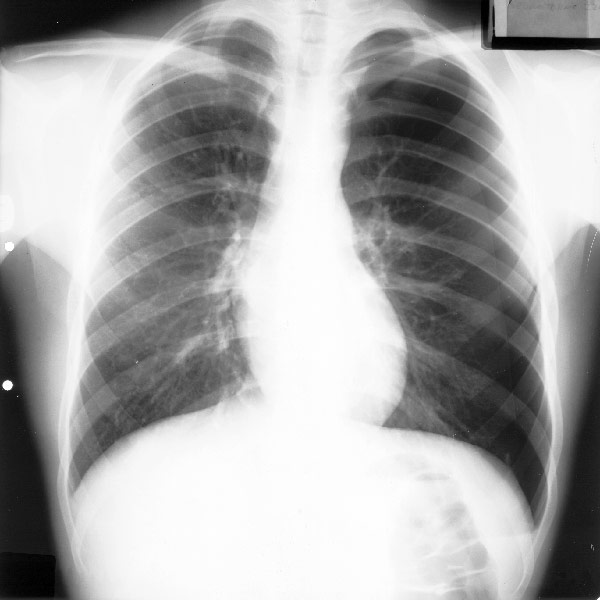

Placa 46